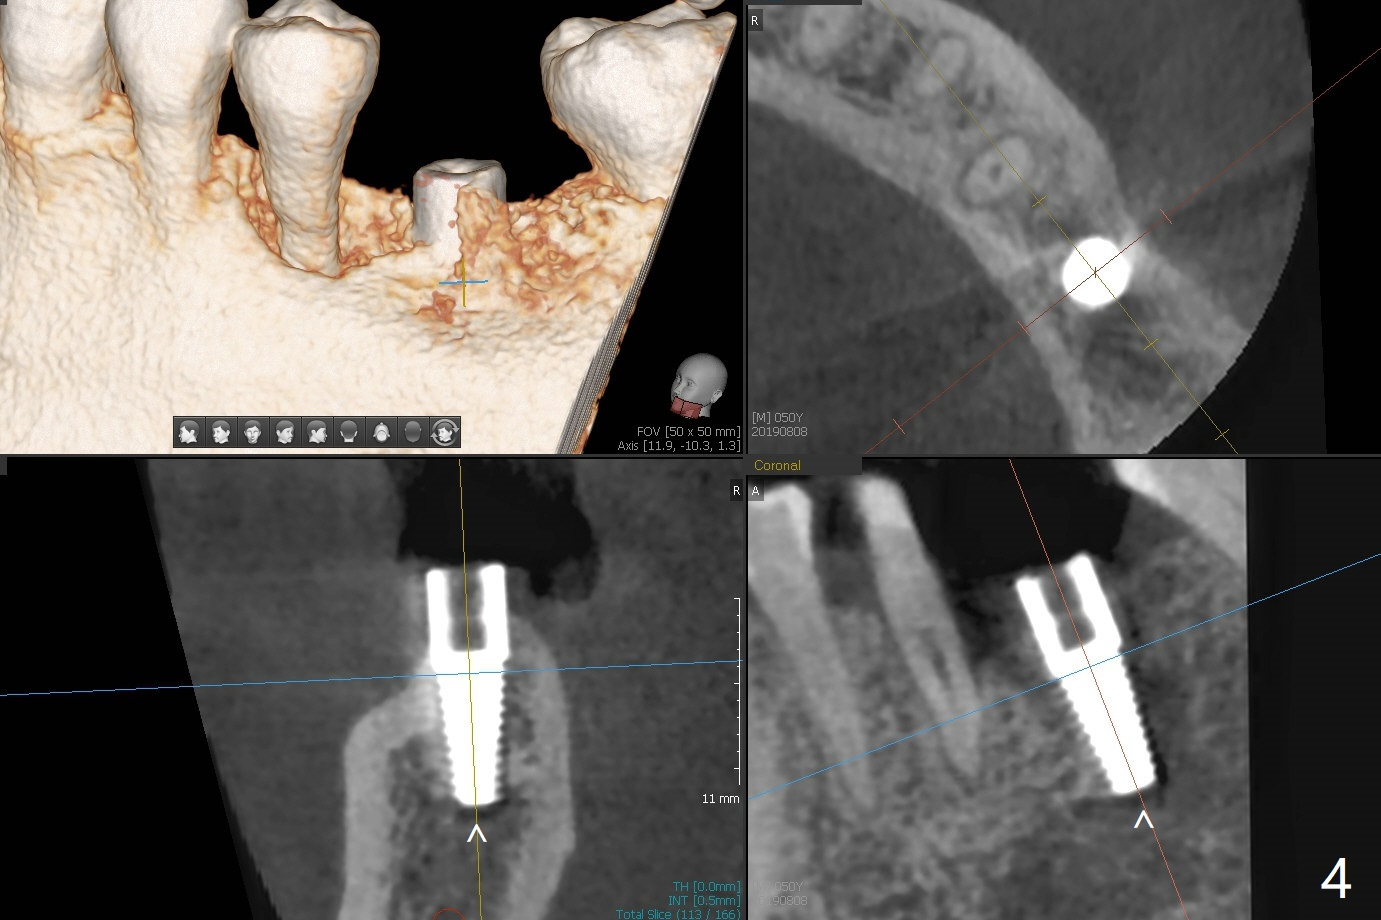

After 4x11.5 mm drill with 10.5 mm offset for bone-level implant at #19, a 4.5x14 mm tissue-level tapered tap is used with high torque. The same sized implant is placed in-completely with apical space (Fig.1 ^). Following reuse of the guide and 4.5x7.3 mm drill, the implant is placed deeper easily (Fig.2-4). The implant threads are subcrestal buccally (B (L: lingual plate), as compared to design in Fig.3'). Later the implant is placed a little deeper with insertion torque of 25 Ncm. There is no crestal bone loss 4 months postop (Fig.5). Waterlase is used for gingivectomy without anesthesia or burn after placing a 4x5 mm abutment. The access is difficult due to severe bone loss. There is no gap between the implant threads (osteointegration) 9 months postop/immediate post cementation (Fig.6 < (coronavirus)), although the crestal bone has lost. After cementation, the tooth #20 has no mobility; note bone loss around the root of #20 (Fig.5). In spite of the residual cement, there appears no bone loss 2 months postop (Fig.7). Instead the distal crestal bone is more organized.